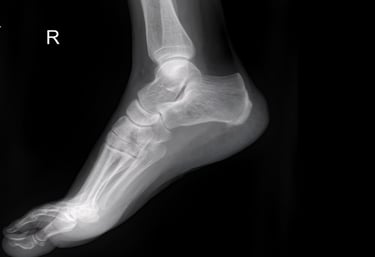

Foot & Ankle X-rays

Precise digital imaging for foot, ankle, and toe injuries, including fractures and joint alignment. We provide high-resolution views for orthopedic diagnostics and occupational health clearances.